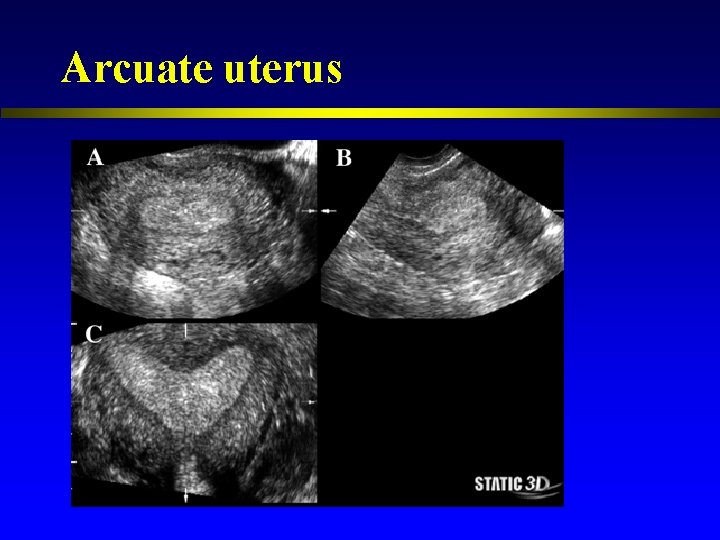

Arcuate uterus

Congenital uterine anomalies l l l Associated with a range of adverse reproductive outcomes Septate uterus had a higher proportion of 1 st trimester loss compared with women with a normal uterus. Women with an arcuate uterus had a greater proportion of 2 nd trimester loss and preterm labor. (Woelfer et al. , 2001)